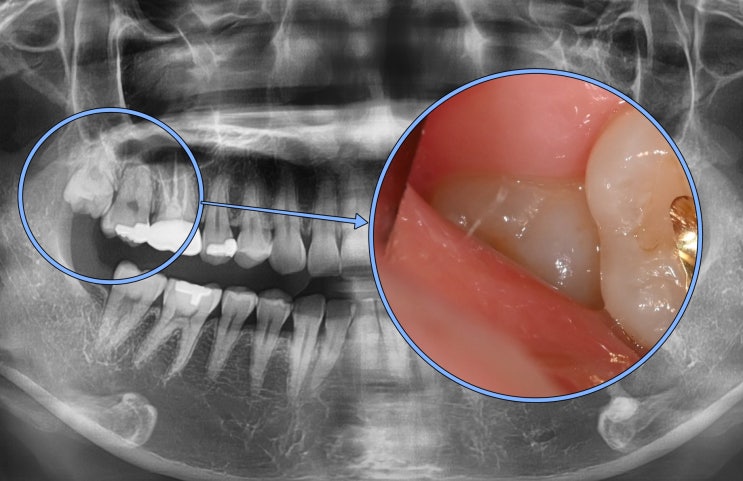

신촌역치과 정기검진의 중요성 다수의 충치 재발, 인레이, 신경치료

안녕하십니까, 대표원장 조민기입니다. 여러분들께서는 정기검진 을 받으신지 얼마나 되셨나요? 많은 분들...